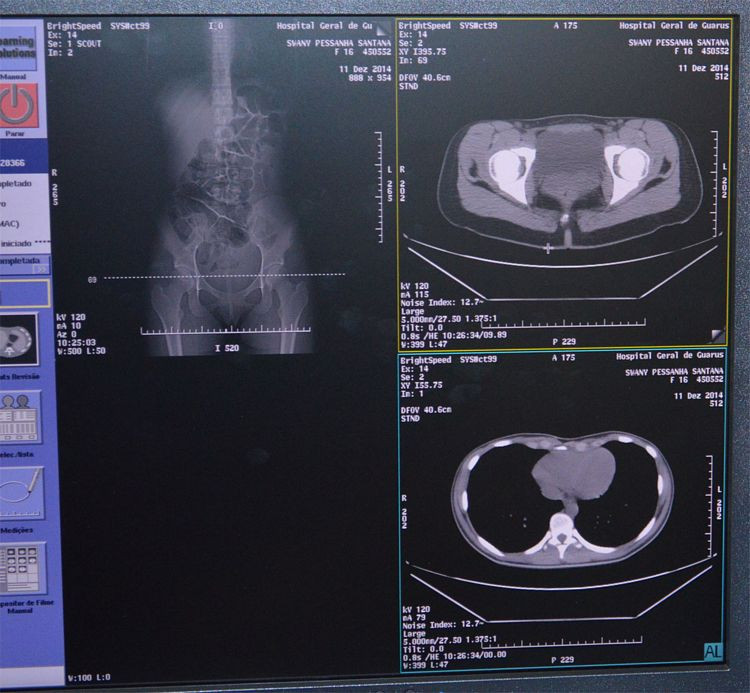

O novo tomógrafo do Hospital Geral de Guarus (HGG) está instalado e em funcionamento. O equipamento já foi testado e está sendo usado no treinamento das equipes médica e técnica que realizam as tomografias, na unidade hospitalar.

— Estamos apresentando para o pessoal as funcionalidades deste novo equipamento. Além da qualidade de resolução de imagens, outro ponto que merece destaque é a carga de radiação, que é 40% menor que a do tomógrafo antigo — afirmou o técnico da GE responsável pelo treinamento, Vitor Santos.

O novo equipamento permite a realização de tomografias computadorizadas em pacientes de até 227kg e conta com a tecnologia multislice, a mais avançada existente no mercado. O método permite importante redução do tempo do exame, além de uma definição precisa de imagens.